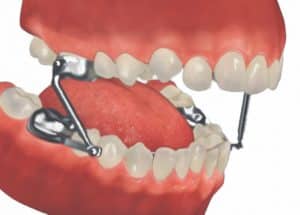

Additional appliances used in orthodontic treatment may include the following: -Temporary Anchorage Devices (TADs): mini-screws used temporarily to apply extra pressure to teeth. -Rubber Bands (also called Elastics): used to apply force to teeth. -Additional appliances such as HERBST and RPE may be used.

Orthodontic appliances

Orthodontic treatment can be done by many sorts of appliances, which most people call a 'brace'.

What is a fixed brace?

So a fixed brace is used. This has brackets and bands which are temporarily stuck to the teeth. A flexible wire joins all the brackets and allows the teeth to be moved. You can't take the appliance out yourself, so it is called a fixed appliance.

What is a functional brace?